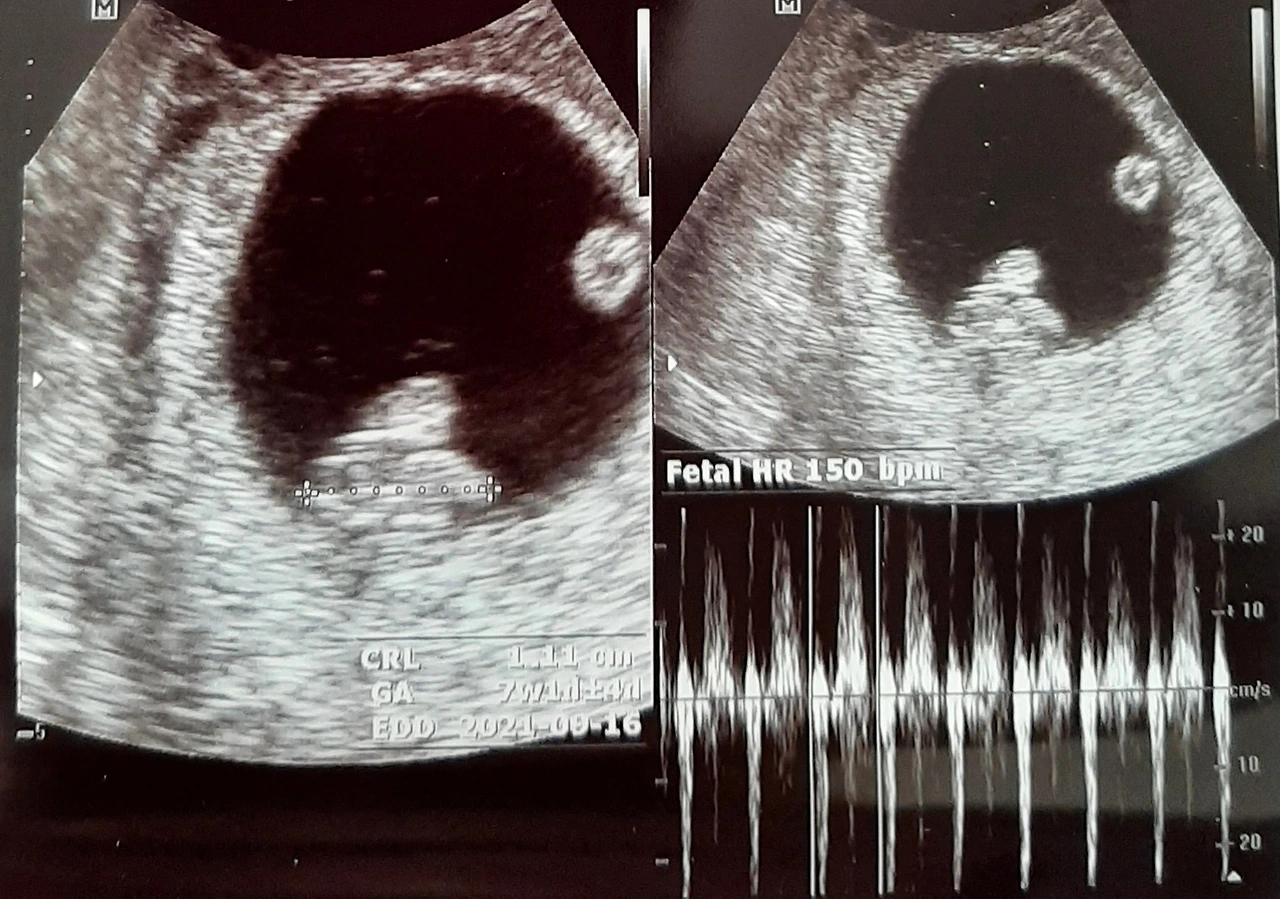

"쌍둥이네요. 반짝임이 두 개 보이죠?“

하나의 작은 집 안에서, 두 개의 점이 나란히 반짝이고 있었다. 세상에. 우리가 부모가 된다는 것도 아직 실감이 나질 않는데, 두 명의 아이를 품었다니. 그 조용한 반짝임 이후, 나와 남편 인생의 많은 것들이 변했다.

그리고 딱 일주일 뒤, 그 조그마한 점 안에 두 개의 반짝임이 나타났다.